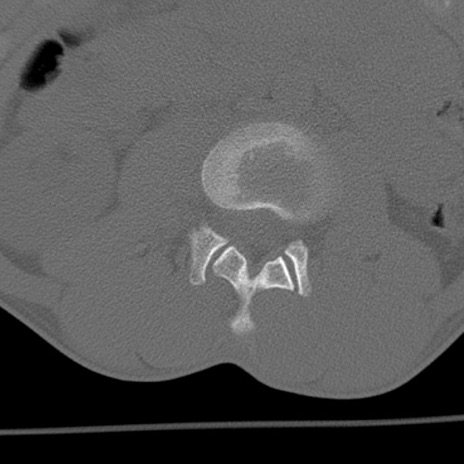

症例3 腰椎CT(横断像)

腰椎CT